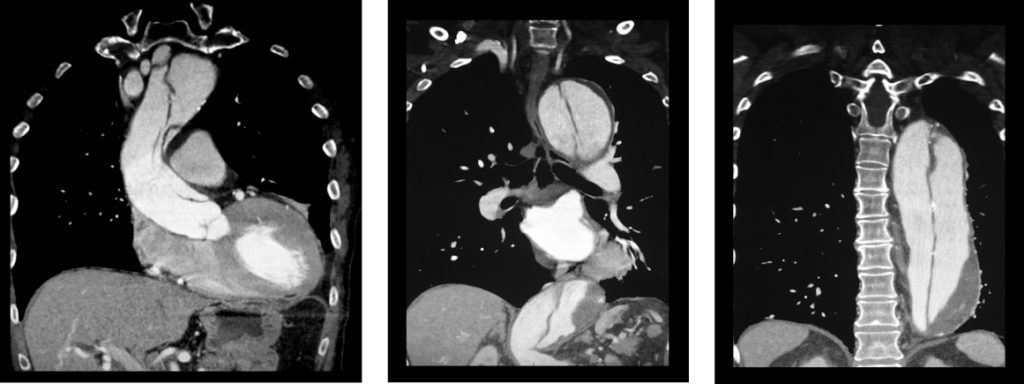

Figure 4 CTA Showing A Type A Aortic Dissection Extending Along The

Thoracic Aortic Dissection CT Radiology At St Vincent s University

Computed Tomography With Contrast Enhancement In A Patient With Acute